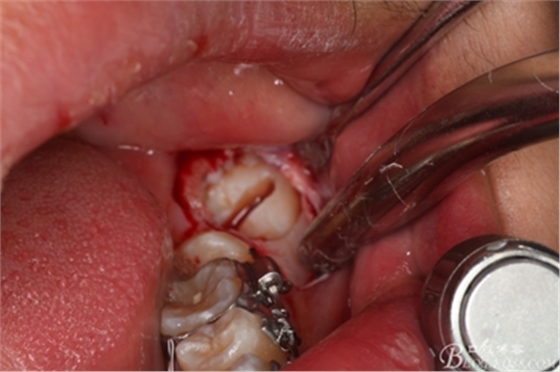

圖11.縱分牙冠

圖12.縱分完成的牙冠